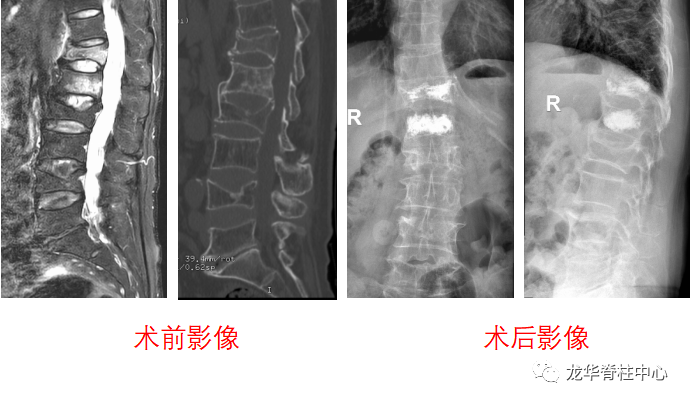

针对该患者的诉求,张昊主任与其团队进行了反复的讨论并分析小王的问题,首先,小王才15岁,但腰椎间盘突出明确并伴有椎体后缘离断,神经受压明显,导致下肢疼痛、麻木,严重影响日常生活和学习,经过一段时间保守治疗,仍反复,并且越来越明显了,因此针对青少年的腰椎间盘突出症患者治疗方面该如何定夺呢?张昊主任分析,结合该患者的特殊性,又要考虑患者以后的影响,把相关治疗方案以及相应的风险等事宜详细告知陈女士,最终在微创理念下采用脊柱内镜下腰椎间盘摘除技术为小王进行手术,手术切口1cm,术后症状缓解,恢复良好,效果非常满意,第二天顺利出院。

术前影像

术后影像